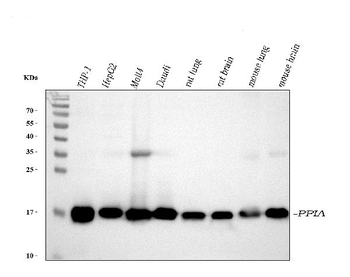

Anti-Cyclophilin A/PPIA Antibody [orb19174]

FC, ICC, IF, IHC, IHC-Fr, WB

Human, Mouse, Rat

Rabbit

Polyclonal

Unconjugated

10 μg, 100 μgCYPA Rabbit Polyclonal Antibody [orb100498]